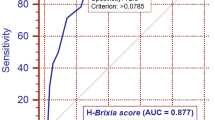

We next evaluated the importance of the variables encompassed in the RF algorithms for intra-hospital mortality and intubation prediction. In the RF model for mortality prediction, the most important nodes (importance > 50) were C-reactive protein, age, PaO2/FiO2, glycemia, SpO2 on admission, a well-aerated parenchyma, lactate dehydrogenase, GGO, lymphocytes, other consolidation/fibrosis, and symptom onset (Fig. 2A). In the RF tree model for intubation prediction, the most important nodes (importance > 50) were PaO2/FiO2, a well-aerated parenchyma, C-reactive protein, GGO, other consolidation/fibrosis, glycemia, lactate dehydrogenase, lymphocytes, and age (Fig. 2B). The variables having more than 10% of missing values were excluded from the predictive tool (i.e., BMI, fibrinogen, procalcitonin, ferritin, and troponin). The balanced accuracy in predicting intra-hospital mortality was 0.89 (κ value = 0.72; AUC = 0.73) (Fig. 3A), whereas the balanced accuracy in predicting intubation was 0.9 (κ value = 0.75; AUC = 0.74) (Fig. 3B). When the quantitative CT analysis variables were removed from both RF models, the accuracy of the model predicting intra-hospital mortality dropped to 0.75, whereas that of the model predicting intubation fell to 0.69 (Fig. 4A, B).